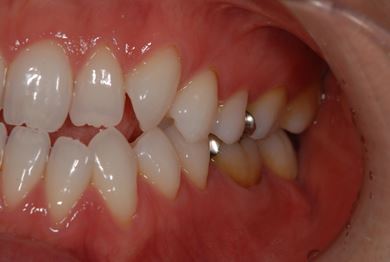

性別/年齢 女性 / 32歳

主訴 銀歯を白い歯にしたい。

治療方針 セラミック治療にて、審美的回復を行う。

治療内容 ハイブリッドセラミッククラウン1本、ハイブリッドセラミックインレー1本

治療後